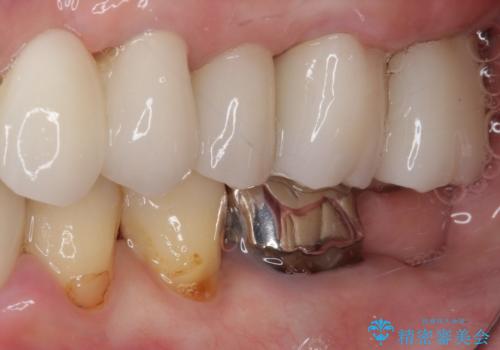

- 歯を磨く度に奥歯から出血するとのことで来院された患者様です。

歯周ポケット検査を行ったところ、6-8mmの歯周ポケットが散見され(正常では3mm以下)、歯周病治療が必要と判断されました。

仮歯に置き替え、歯周外科処置(APF、歯肉弁根尖側移動術)による歯周ポケット除去を行った後に、オールセラミッククラウンにて補綴することとしました。

歯周外科処置により歯周ポケットを除去することができ、クラウン装着後はブラッシング時の出血や歯肉の腫れが気にならなくなりました。